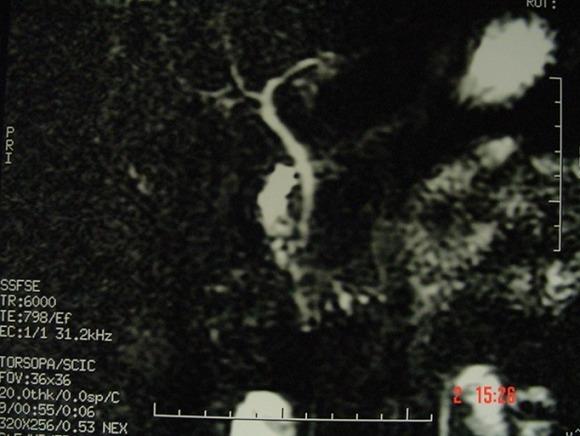

Gallbladder agenesis is a rare congenital anomaly. This study aimed to highlight the epidemiological aspects of this condition as well as the peculiarities of its diagnostic and therapeutic management through three case reports. Two adults were admitted to Hospital with hepatic colics and dyspepsia. Ultrasound showed multilithiasic scleroatrophic vesicle. In one of the two patients, CT scan results showed a stone at the level of scleroatrophic vesicle. These two patients were wrongly operated for vesicular lithiasis by using conventional method. The absence of gallbladder was detected during surgery. In order to confirm post-operative diagnosis, the first patient underwent biliary MRI. The other patient was lost to follow-up. The third patient was a 13-year old child hospitalized with acute pancreatitis. Vesicular agenesis was suspected based on its scannographic aspect and then confirmed using biliary MRI. This patient didn't underwent surgery.

胆囊缺如是一种罕见的先天性异常。本研究旨在通过三例病例报告强调该病症的流行病学方面及其诊断和治疗管理的特点。两名成年人因肝绞痛和消化不良入院。超声显示为多发结石性硬化萎缩性胆囊。在这两名患者中的一名,CT扫描结果显示硬化萎缩性胆囊处有结石。这两名患者通过传统方法被误诊为胆囊结石并接受了手术。手术中发现胆囊缺失。为了确诊术后诊断,第一名患者接受了胆道MRI检查。另一名患者失访。第三名患者是一名13岁儿童,因急性胰腺炎住院。根据扫描图像怀疑胆囊缺如,随后通过胆道MRI得以确诊。该患者未接受手术。